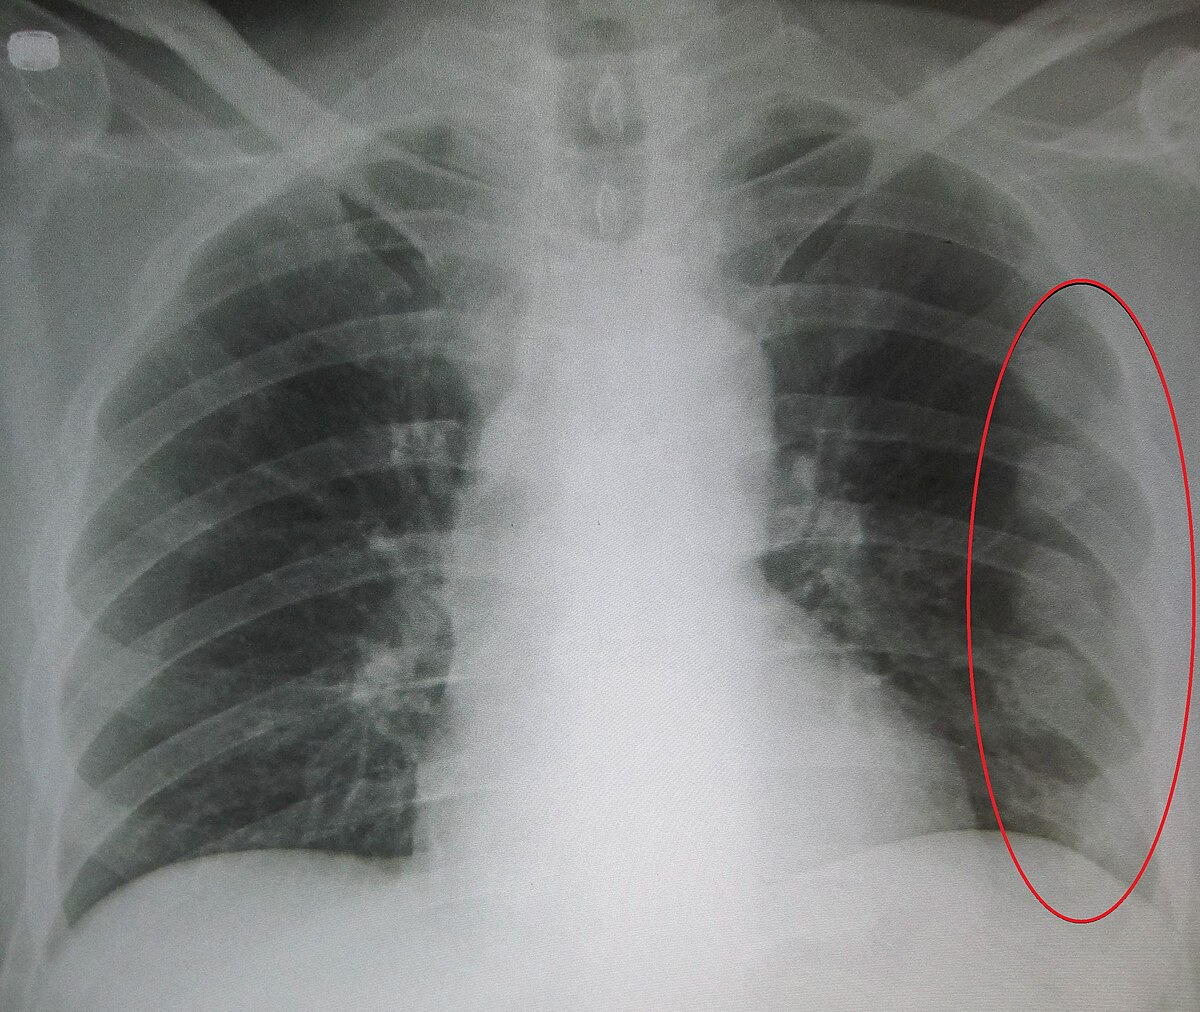

갈비뼈 금이 갔을 때의 증상

갈비뼈가 금이 갔을 때에는 다음과 같은 증상이 나타날 수 있습니다:

- 통증: 금이 간 부위 주변에서 강한 통증이 느껴집니다.

- 불편한 움직임: 갈비뼈가 금이 갔을 때는 그 부위를 움직이는 것이 어려울 수 있습니다.

- 부종: 금이 간 부위 주변에 부종이 생길 수 있습니다.

- 반응성: 갈비뼈가 금이 간 부위에 압력이 가해지면 통증이 증가할 수 있습니다.

이러한 증상이 나타난다면 즉시 의료진의 도움을 받는 것이 중요합니다.